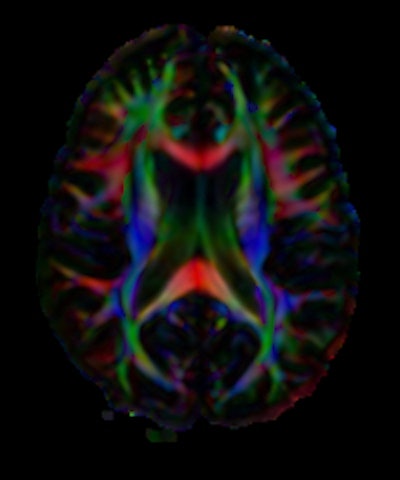

| Color-coded orientation map of a human brain calculated from diffusion tensor imaging. Each pixel contains information about the eigenvector (color) and amount of diffusion anisotropy (intensity) that summarize the information contained in the 3 x 3-matrix tensor. Image courtesy of the National Institutes of Health. |

In a history of computed imaging posted in July 2009 at Nature Precedings, Filler wrote that his 1992 patent covered all of the primary steps for performing DTI and tractography, including a 3D measurement scheme that tracked the direction of diffusion, permitting its color-coded presentation.